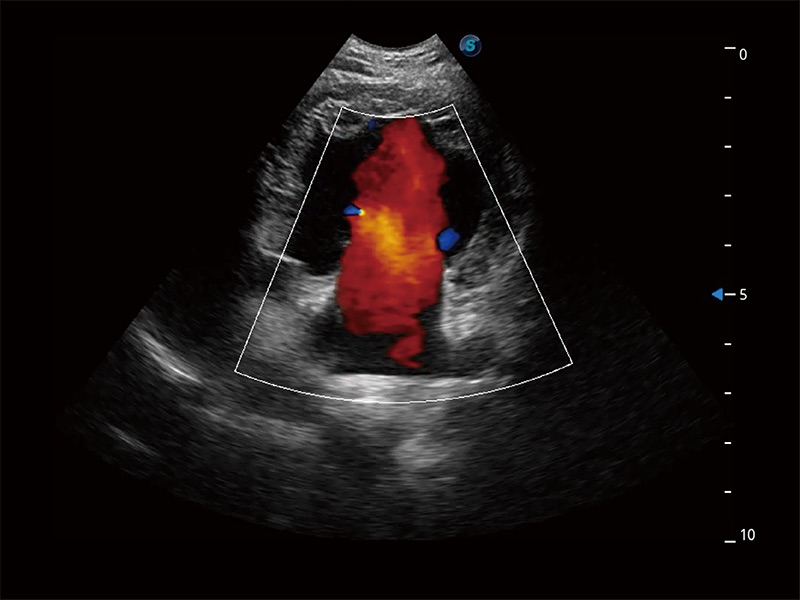

ProPet 80 配备了丰富的心脏探头群、先进的成像技术和专业的心脏测量工具,可帮助动物医生为不同体型和生理结构的动物提供心脏和心肌功能的全面评估。

实时用颜色表示心肌组织运动,观察和定量组织的运动情況,对快速检测与评估心肌的灌注和活性、电传导及心肌收缩和舒张功能等均能提供重要的诊断信息。

能够增加心肌组织与血流之间的区别。对于心脏扫查困难的动物,可提供更好的心内膜边界的显示。